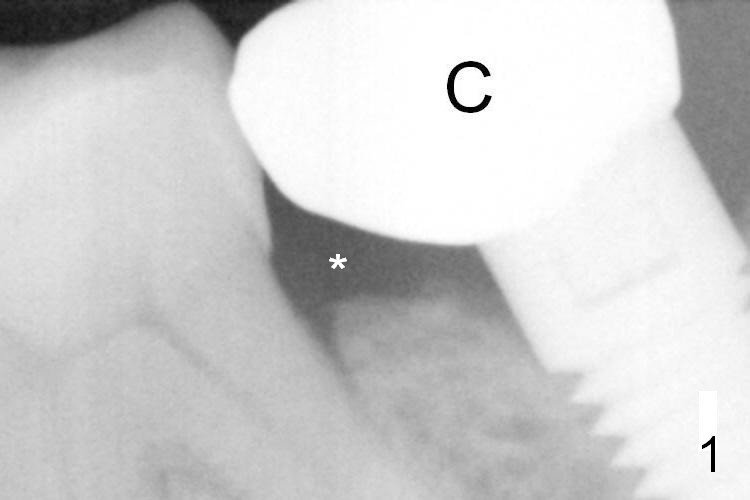

A 65-year-old woman was pleased with functionality of the implant crown at #18 immediately post cementation (Fig.1 (taken 6 months post cementation).  In 2 years and 8 months, she complains of gingival irritation after food impaction.  Although the proximal contact is slightly light with floss, the gingival embrasure feels to be extremely large (Fig.1 *).  When the crown is to be remade, increase the vertical contact (Fig.2 red line) to close the gingival embrasure as much as possible.  PA taken immediately before redo shows that there is no gap between #18 and 19 (Fig.3).  When the crown is being cut off, the gingiva is tender.  It appears that the existing crown (made by Classic Craft) has overextended margin.  When the new crown is being fabricated, trim the margin of the die very well.   The margin of the new crown should be shorter (Fig.3 red curved line).